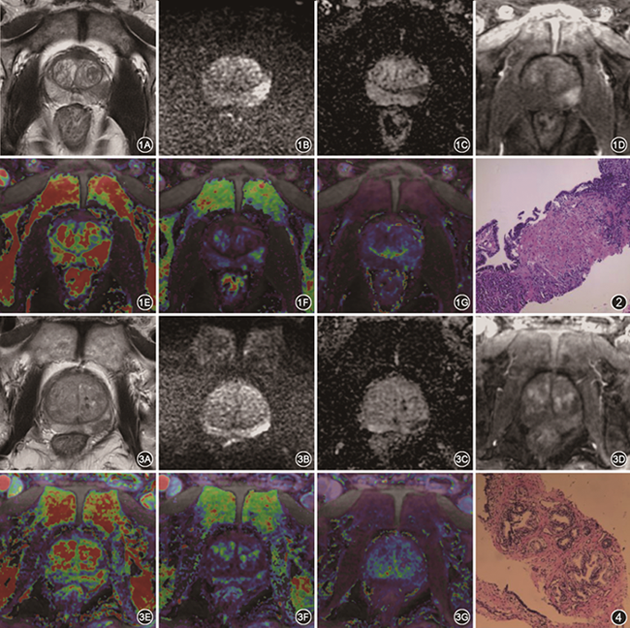

3.图像后处理:将MRI图像导入GE ADW 4.7后处理工作站,由两名放射科医师(在前列腺诊断方面分别有3年和5年经验),参考PI-RADS v2.1对所有病灶的病理结果与之对应的MRI图像达成共识。对于多灶病例,选取Gleason评分最高的病灶。ROI的选取避开所有影响因素(尿道口、血管、精囊腺等)。在GenIQ软件包打开DISCO图像,参考T2加权成像(T2WI)和MUSE-DWI图像,选择病灶强化最显著时相,分别在病灶最大层面及其上下两层勾画ROI(10~30 mm2),同时在容积转移常数(volume transfer constant,Ktrans)、速率常数(rate constant,Kep)、血管外细胞外体积分数(extravascular extracellular volume fraction,Ve)伪彩图上自动生成相应的ROI及参数值,取平均值。然后在READYView软件包中打开MUSE-DWI图像,将ROI匹配到MUSE-DWI图像上,同时在表面扩散系数(ADC)图上自动生成相应的ROI及ADC值,取平均值。最终的结果取两名放射科医师测量结果的平均值;病例图像见图1, 2, 3, 4。

注:PSA为前列腺特异性抗原;T2WI为T2加权成像;MUSE-DWI为基于复合灵敏度编码的高分辨率扩散成像;ADC为表观扩散系数;DISCO为基于笛卡尔采集的K空间共享三维容积快速动态成像;Ktrans为容积转移常数;Kep为速率常数;Ve为血管外细胞外体积分数